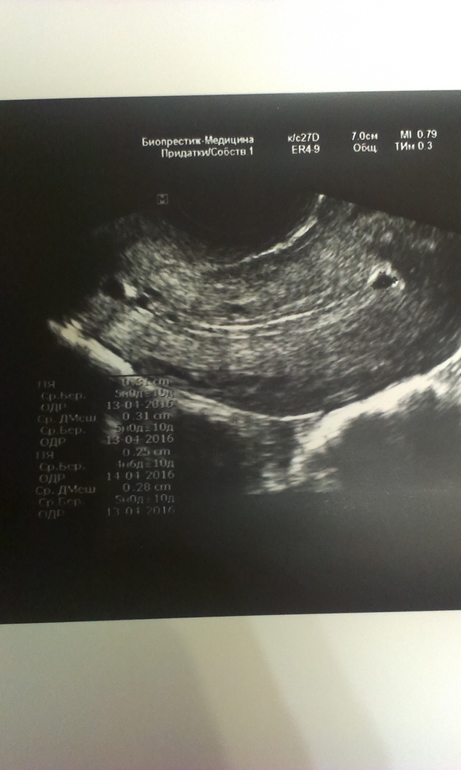

Девочки была на узи 12 августа, врач усмотрел или синехею в матке или Зб малого срока. 7 дц, в яичнике зреет фолликул, 8 мм тогда, сегодня тест на О положительный. Чем грозит синехея эта

Жалко эндометрий какой не указано. Синехею увидела с краю на дне матки.

Синехии спутать с плодным яйцом невозможно, у них абсолютно разные эхоструктуры. Вам следует сдать кровь на ХГЧ. Если результат отрицательный, то не синехию надо исключать, а полип эндометрия, желательно у другого доктора.

Ваще я бы после такого узи пошла к другому узисту - заключение похоже на бредни. Какая зб на 7дц при растущих фолликах? И синехии по узи ваще-то не ставят. И уж как спайку можно с плодным яйцом перепутать, я ваще не представляю

Синехия-это спайка,гистеру делают для постановки точного диагноза,по узи только предполагают.Сделать узи в другом месте,какой бред тебе наговорили(